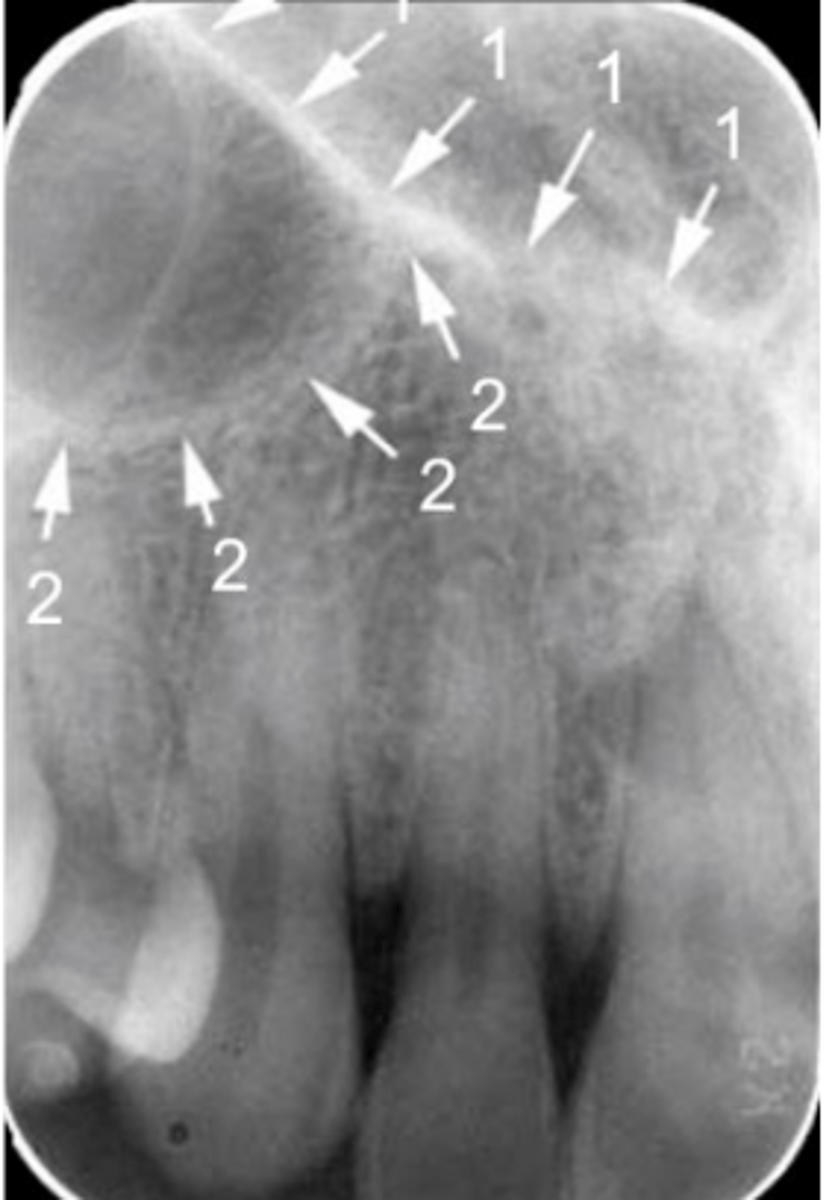

Black arrow - Nasal septum

White arrow- nasal conchae

Identify both structures

New cards

Black arrow - Floor of the nasal cavity

White arrow- maxillary sinus

Identify the structures

Floor of the nasal cavity

Name the line indicated by arrows labeled #1.

<p>Name the line indicated by arrows labeled #1.</p>